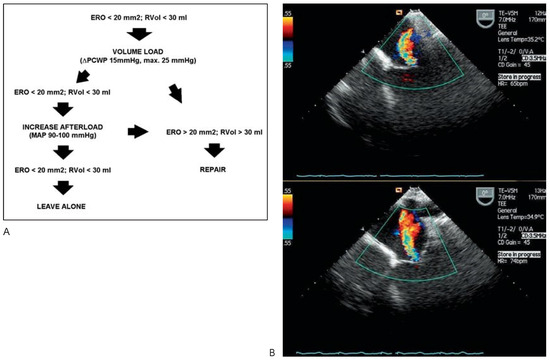

Ischaemic mitral regurgitation (IMR) is defined as functional MR with systolic restriction of leaflet motion, apical and lateral displacement of the subvalvular apparatus, and annular dilatation in the presence of a morphologically normal mitral valve. IMR is usually caused by LV dilatation in the setting of ischaemic or idiopathic dilated cardiomyopathy (CMP). Left ventricular dilatation leads to dilatation of the mitral annulus and to apical and lateral displacement of one or both papillary muscles with tethering of the valve leaflets and consecutive IMR. Therefore, IMR begets IMR with a vicious cycle of increased volume load leading to ventricular dilatation, leading to more IMR etc. Although MR is thought to unload the LV, wall stress is increased due to LV dilatation according to Laplace’s law. IMR is therefore thought to be primarily a ventricular and not a valvular problem. IMR is known to be prognostically important irrespective of LV function and of IMR severity at rest, because it is very dynamic and sensitive to loading conditions. IMR may frequently be severe during daily activity inducing LV failure on the long term. Therefore, dynamic testing is becoming the method of choice for assessment of these patients. Medical therapy has been shown to be inferior to surgery in the setting of IMR. Although still controversial with regard to what surgical method may be best not only to correct IMR, but also to induce a change in LV size and shape-the so-called reverse remodeling-surgical treatment is indicated with a docu­mented effective regurgitant orifice area (EROA) > 20 mm2 and a regurgitant volume (Rvol) > 30 mL by transthoracic echocardiography (TTE) at rest or with an increase of EROA > 13 mm2 in exercise TTE. Furthermore, intraoperative provocative testing may help identify significant IMR. Correction of IMR is usually done by restrictive annuloplasty with aggressive under­sizing of a conventional closed and semirigid annuloplasty ring. Improved LV function and a decreased need for cardiac transplantation has been seen in published series. With the ad­vent of new rings and devices specifically designed for correction of IMR, results may further improve. Modern specific annuloplasty rings are designed to correct the down- and outward displacement of the subvalvular apparatus by inducing an acute valvular and ventricular reshaping. With the choice of various models, IMR may be corrected more precisely by selecting a type of ring according to the geometry of the regurgitant jet and the dis­tortion of the valve leaflets. In case of ischaemic CMP, not only complete revascularisation, but also resection of aneurysmatic myocardial scar tissue and surgical LV remodeling is usually performed. With the help of new devices such as the ACORN CorCap® device further dilatation may effectively be prevented and may even improve LV function in selected patients. Alternatively, cardiac transplantation, implantation of an assist device for destination therapy in patients not qualifying for cardiac transplantation or resynchronisation therapy may be evaluated in very advanced cases. Full article

Show Figures

Figure 1